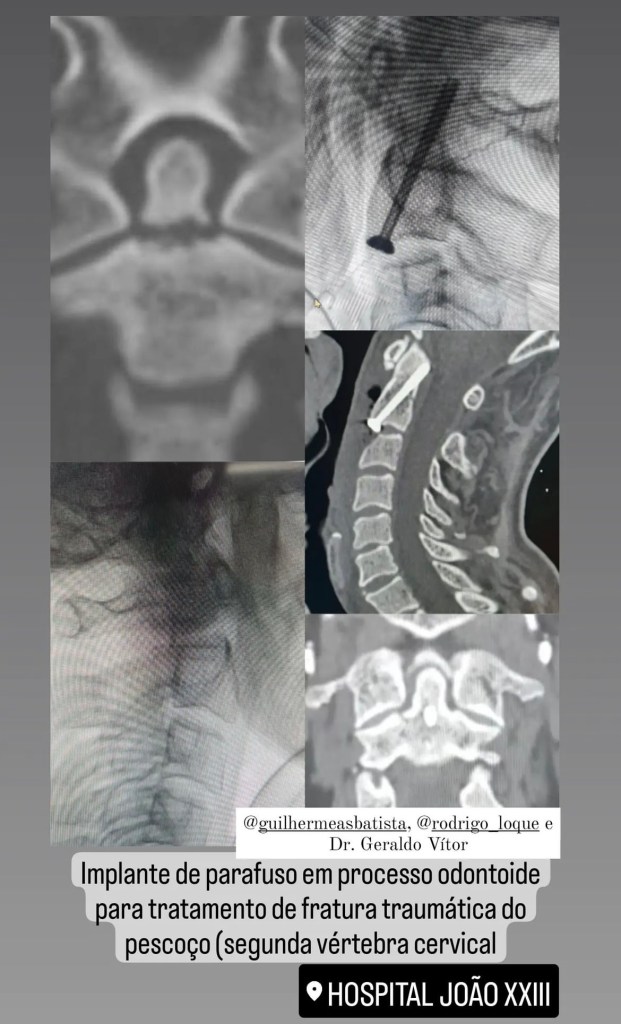

GALERIA De cirurgias

Abaixo você pode conferir imagens de algumas cirurgias já realizadas por Dr. Marcelo Camargos. Caso tenha alguma dúvida ou interesse, não deixe de fazer contato para maiores esclarecimentos!